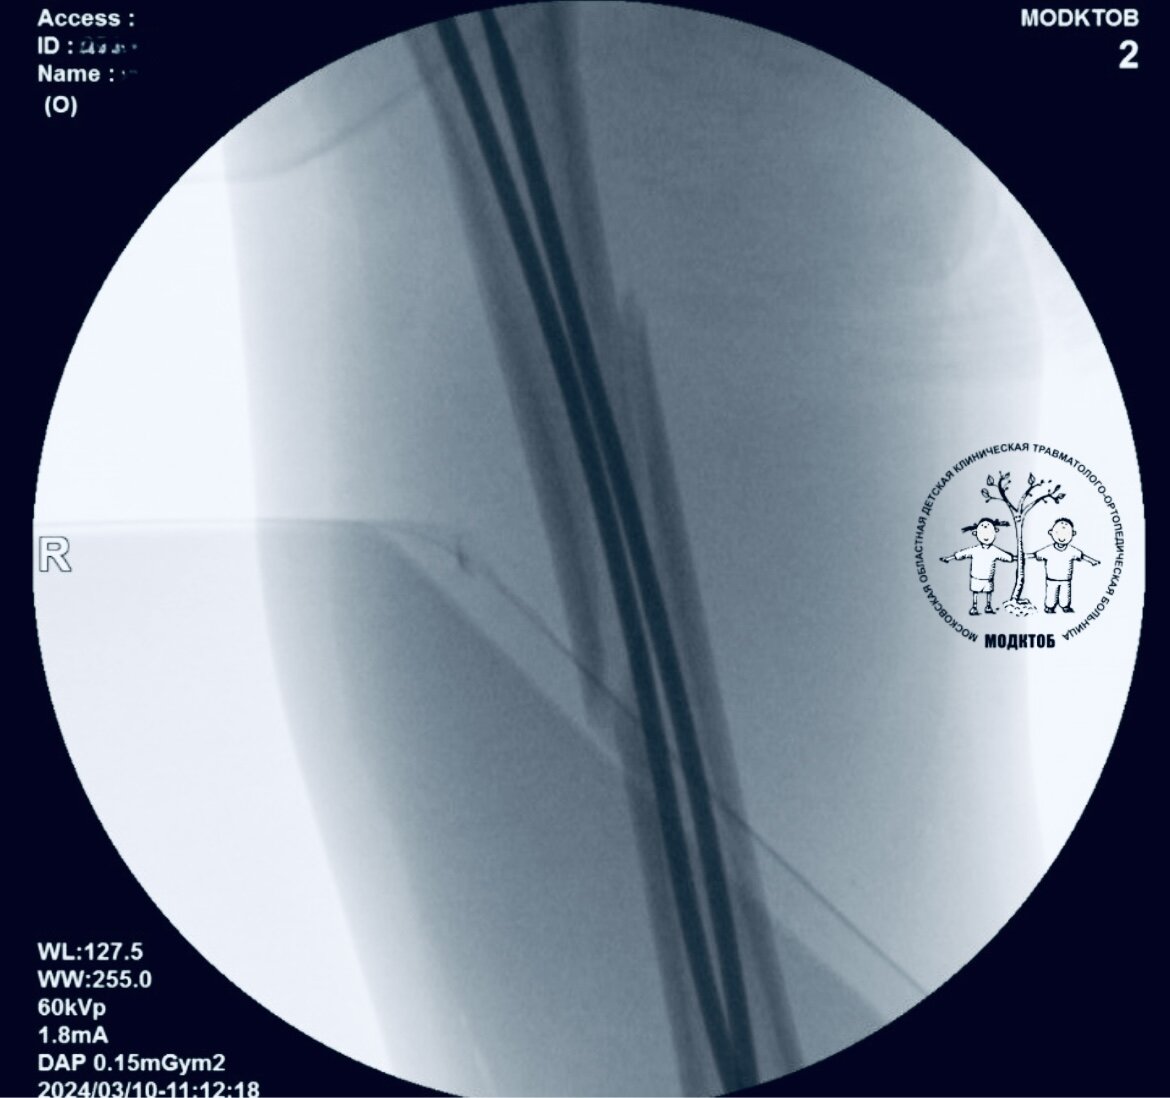

🚑 Прямо с соревнований по самбо бригадой скорой помощи в МОДКТОБ доставлен ребенок с переломом бедра.

💬 «Бедро — самая большая кость в организме человека и нарушение анатомии данного сегмента может привести к тяжелому сбою функций передвижения. По экстренным медицинским показаниям ребенку проведено хирургическое лечение. Мы восстановили анатомию бедра, установив через два точечных прокола титановые стержни», — прокомментировал врач травматолог-ортопед Куваев Виталий Анатольевич.

💉 Когда кость полностью восстановится, планируется удаление фиксаторов.